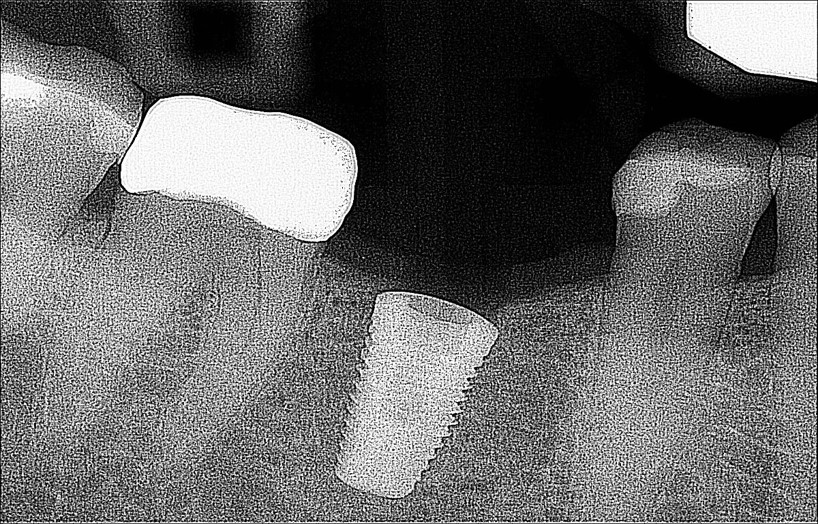

A dental Implant is a titanium “root” that integrates directly with the surrounding bone and replaces the function of the natural tooth. Neoss Implants are made using the best quality medical grade titanium, which is well known for its proven biocompatibility, and have a treated surface to facilitate bone integration.